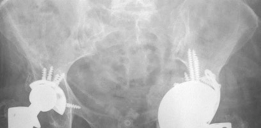

5. Severe Uncontained Defects / Pelvic Discontinuity (Paprosky Type IIIB/IV):

• These cases may require a combination of HPM augments and cones, or even custom triflange acetabular components.

• Triflange Components: Custom HPM triflange components are specifically designed based on pre-operative CT scans to match the complex defect, providing fixation to the remaining ilium, ischium, and pubis, essentially creating a new acetabulum. This is a salvage option for extreme cases.

• Reconstruct the columns first, using HPM augments or structural allograft, then proceed with cup fixation.